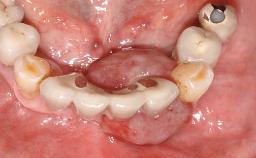

Michael Bornstein

Basel, Switzerland